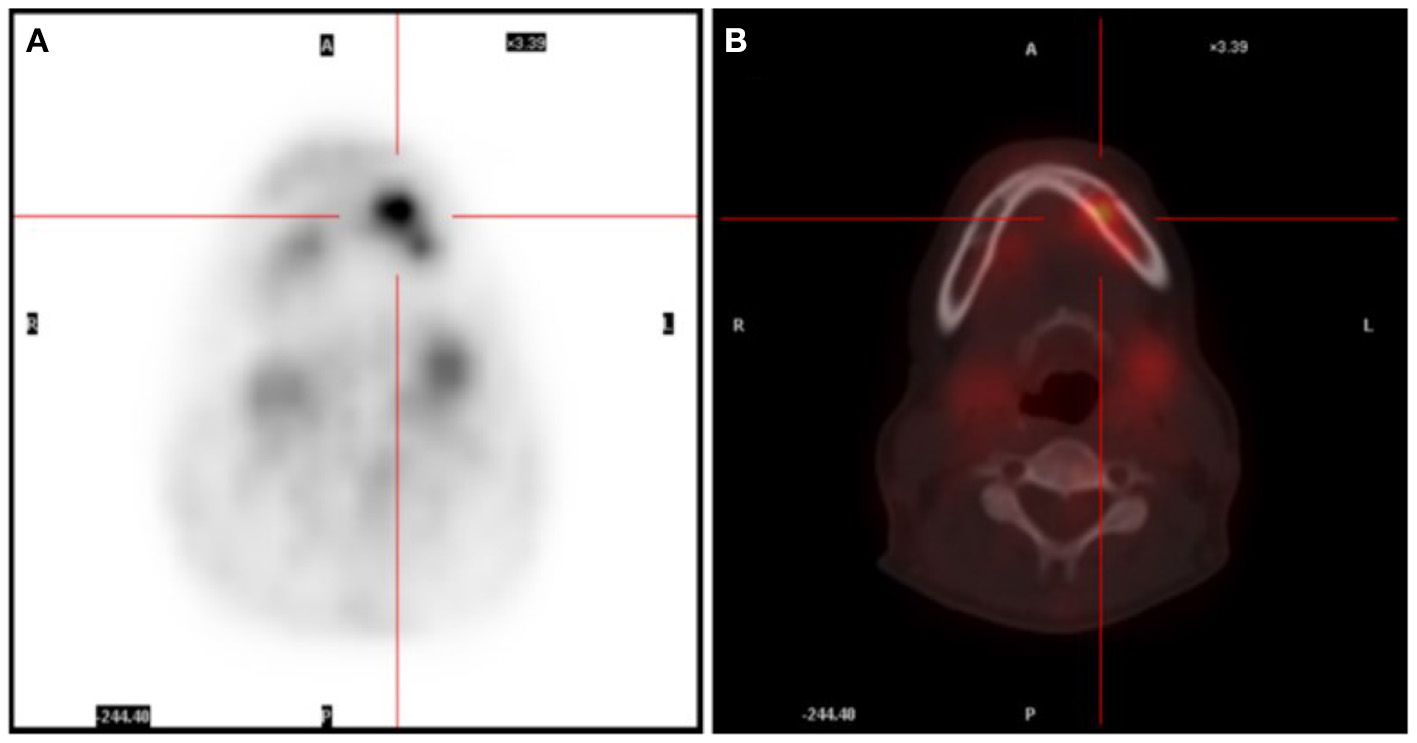

A 52-year-old female presented with recurrent fever for more than 1 month, with a highest temperature of 38.8°C and chills. The patient experienced numbness in her left mandible and slight pain in her left teeth. The blood routine examination was normal, C-reactive protein (CRP) was 7.33 mg/L, erythrocyte sedimentation rate (ESR) was 42 mm/h, rheumatoid factor was 5.7 IU/ml, anti-o was 89 IU/ml, anti-nuclear antibody, alpha work, Epstein Barr virus, cytomegalovirus DNA, tumor biomarkers were negative. The head (including the mandible region), chest, and abdomen CT showed no active lesions, and echocardiography showed no abnormality. Prior to hospitalization, the patient had a full-body positron emission tomography (PET) scan performed, which revealed an elevated glucose metabolism in the left alveolar branch of the mandible (standardized uptake value (SUV) max = 5.87) (Figure 1). In addition, multiple small nodules were seen in both lungs and exudative changes in the lower lobes of both lungs and splenomegaly were observed. These findings were also confirmed by chest, abdomen, and pelvis enhanced CT. As a result, microbial infection was primarily suspected. Following 4 weeks of antibacterial and antiviral treatment, the patient still had recurrent fever, which was accompanied by perspiration. The blood routine showed the red blood cell count was 3.10*1012/L, hemoglobin was 86 g/L, neutrophil was 1.77*109/L, lymphocyte was 0.71*109/L, CRP was 16.6 mg/L.

Figure 1. (A) PET scan showing an area with glucose uptake in the facial region. (B) PET/CT scan revealing the uptake area located in the left mandible.